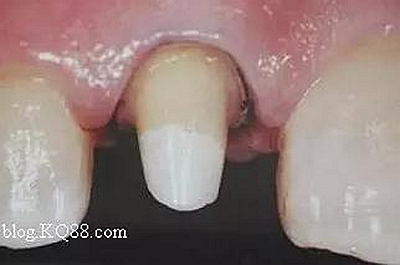

如下圖剩余的組織就過(guò)于薄弱,以后也是一個(gè)安全隱患。

2、去除暫封物。